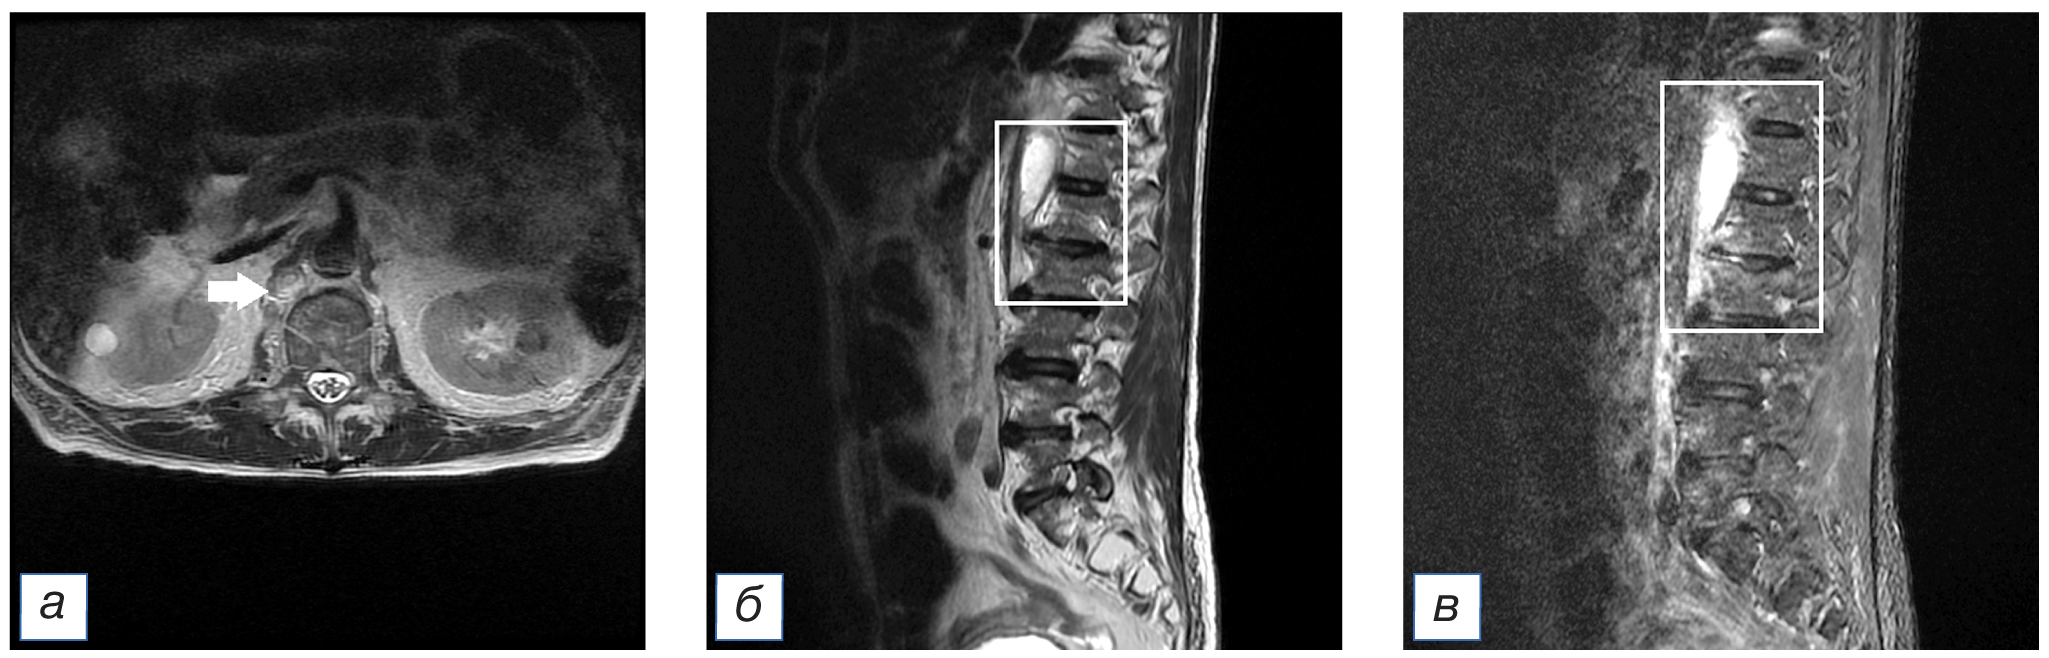

Данные компьютерной томографии (КТ) свидетельствовали о пневмонии второй степени тяжести (рис. 1). Результаты теста на COVID-19 методом полимеразной цепной реакции (ПЦР) были положительными. Сопутствующие заболевания представлены гипертонической болезнью (ГБ), тромбоэмболией легочной артерии (ТЭЛА) от 2019 года и стенозом позвоночного канала на уровне L5–S1 (рис. 2).

Рис. 2. Тот же пациент: магнитно-резонансная томограмма поясничного отдела позвоночника: а — аксиальный срез в режиме Т2-FLAIR на уровне L5–S1; б — сагиттальный срез позвоночного столба в режиме T2-FLAIR; в — сагиттальный срез позвоночного столба в режиме STIR. Стрелками (б, в) указан очаг спондилодисцита. / Fig. 2. The same patient: magnetic resonance imaging of the lumbar spine: а — axial slice in T2-FLAIR mode at the L5–S1 level; б — sagittal slice of the spinal column in T2-FLAIR mode; в — sagittal slice of the spinal column in STIR mode. Arrows (б, в) indicate the focus of spondylodiscitis.